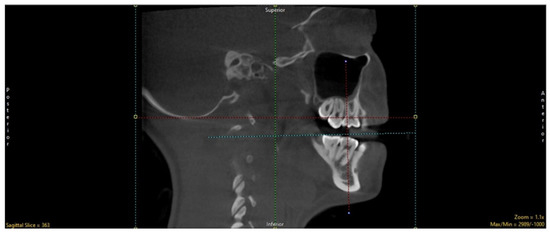

2.1. Selection of Region of Interest (ROI)